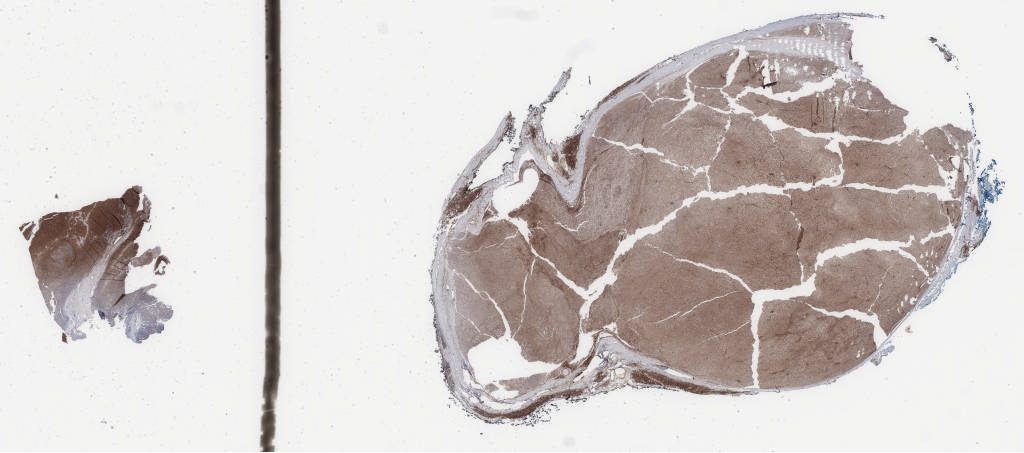

h3k27.svs

131471

x

57883

@

40X